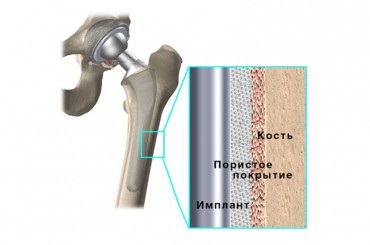

Astăzi, există 2 tipuri de atașare a implanturilor: ciment și necimentate. Uneori este combinația lor numit - hibrid.

Principiul de funcționare este aceeași proteză. Diferente proteze constau într-o varietate de proteze de structurare a calității suprafeței: pulverizare de plasmă bile de titan, fire, picioare de prelucrare abrazive pe tot, acoperire hidroxiapatita, laminat coral komohromovoe.